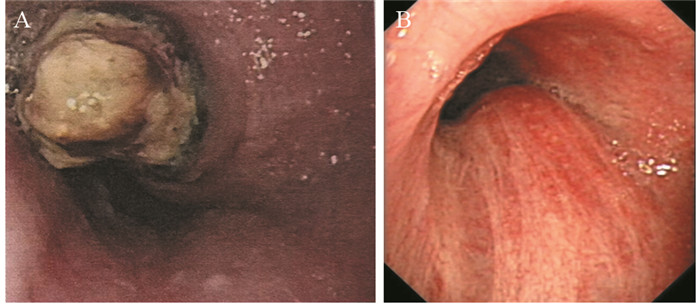

1 病例资料患者57岁,男性,因“进行性吞咽梗阻2月余,咳嗽伴痰中带血一周”于2015年7月16日入院。入院前2月余患者进食干硬食物时感吞咽梗阻。2月以来吞咽梗阻感进行性加重,并逐渐出现咳嗽、咯痰、痰中带血。胃镜提示:食管距门齿27 cm处可见巨大结节样新生物,见图 1A。纤支镜示:左主支气管上段内后壁外压隆起,未见新生物,见图 1B。病理学示:食管内恶性肿瘤倾向低分化癌,见图 2A。免疫组织化学染色:PCK(+)、CK7(+)、TTF-1(+)、CK5/6(-)、P63(-)、CD56(-)、Syn(-)、CgA(-)、NapsinA(-),支持低分化腺癌诊断,但不能确定为肺来源,见图 2A~2D。ALK经免疫组织化学ALK-V及FISH检测(ALK-FISH)均为阳性,见图 2E~2F。食管造影:食管中下段狭窄、管壁僵硬、黏膜破坏,病变长约10.5 cm,见图 3A。胸部增强CT见左肺下叶后基底段约3.7 cm×3.6 cm肿块影,呈分叶状,见毛刺征;纵隔及双肺门淋巴结肿大融合呈团块,最大者短径约3.0 cm;后纵隔约10.1 cm×5.8 cm肿块影,压迫食管,与食管壁分界欠清,见图 4A、4C、4E。头部MRI提示颅内转移瘤。上腹部CT、全身骨显像未见肿瘤转移征象。CEA 31.87 ng/ml,CYFRA21-1 15.49 ng/ml。颈部彩超提示右侧锁骨上区肿大淋巴结,较大约19 mm ×15 mm。入院前2月,体重减轻约20公斤。嗜烟30余年,每天10支。

| A: large esophagus mass with surface nodules (July 10, 2015); B: the uplift in the left main bronchus for external pressure (July 22, 2015) 图 1 纵隔及左肺恶性肿瘤伴食管癌待排患者胃镜及纤维支气管镜图像 Figure 1 Gastroscopy and fibro bronchoscope images of mediastinal and left lung malignancy coupling with suspicion for esophagus cancer patient |

综上,我们考虑该患者诊断为纵隔及左肺恶性肿瘤:左肺低分化腺癌伴纵隔、双侧肺门及右侧锁骨上淋巴结、脑转移,临床分期Ⅳ期,ALK阳性,食管癌不完全排除。经放疗医师评估,考虑食管穿孔风险大,暂不适宜行放疗。患者美国东部肿瘤协作组(ECOG)评分2分,ALK阳性。根据最新NCCN指南推荐:克唑替尼被批准用于ALK阳性转移性非小细胞肺癌。患者和家属要求行克唑替尼治疗。遂于2015年8月3日开始口服克唑替尼(250 mg,2次/天)治疗。患者耐受良好。服药后,自觉吞咽梗阻、咳嗽、痰中带血症状逐渐消失。至2016年7月,患者已服药11月余,未诉吞咽梗阻等不适,ECOG评分0分。复查食管造影提示食管病变缩小,长度约3.0 cm,见图 3B。胸部CT提示左下肺肿块缩小,约2.4 cm×1.9 cm;后纵隔肿块缩小,约1.7 cm×1.5 cm;纵隔及肺门淋巴结缩小,最大者短径约1.2 cm,见图 4B、4D、4F。参照实体瘤疗效评价标准(RECIST 1.1),临床疗效评价为部分缓解。患者治疗效果显著,支持我们的论断。